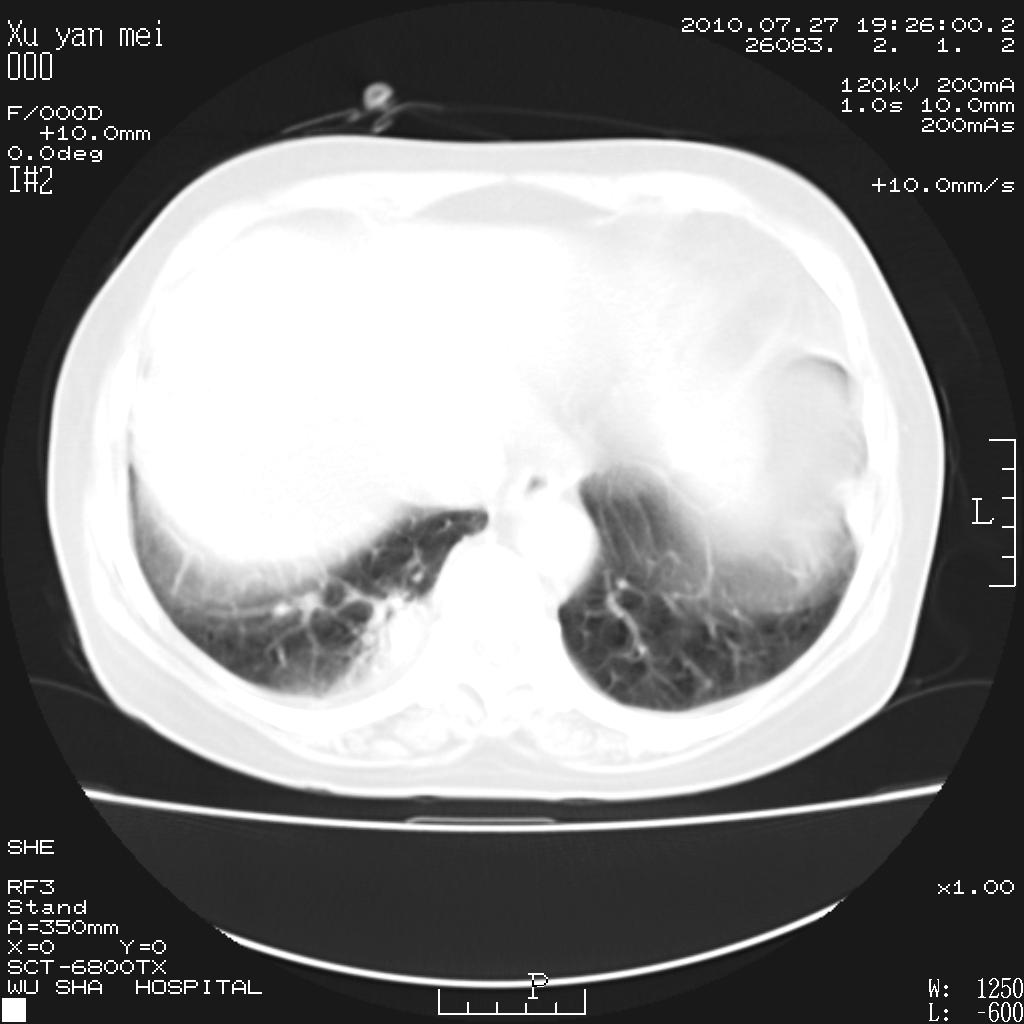

女,60岁,胸痛就诊,右肺结核?炎症?其它?(胸片右侧中上肺野确实看不到什么啊)

1)考虑两肺感染性病变;建议抗炎治疗后复查。2)双侧少量胸腔积液。

1)考虑两肺感染性病变;建议抗炎治疗后复查。2)右侧少量胸腔积液。

双肺炎症可能性大,建议抗炎后复查。右侧胸腔少量积液。双侧胸膜轻度增厚。

考虑两肺感染性病变;不除外肺栓;建议抗炎治疗后复查。